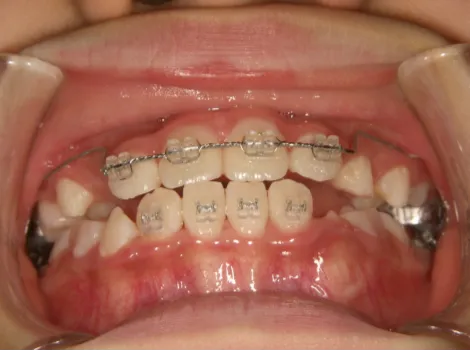

治療前①小2:8y1m 初診

治療スタート:8y2m QH・BHで拡大、前歯の並び替えスタート

| カウンセリング・診断結果 | 前歯が受け口になっていているため、適正な成長へ誘導するために前歯の咬み合わせの改善が必要なことを説明し、診断を希望されたので精密検査へ進みました。 精密検査の結果、骨格的には受け口傾向、下顎前歯の突出、上下ともアーチが小さく凸凹(叢生)が認められ、機能的には低位舌と口唇閉鎖不全があり、口元は上下唇とも突出していますがコンケーブになってないことがわかりました。 |